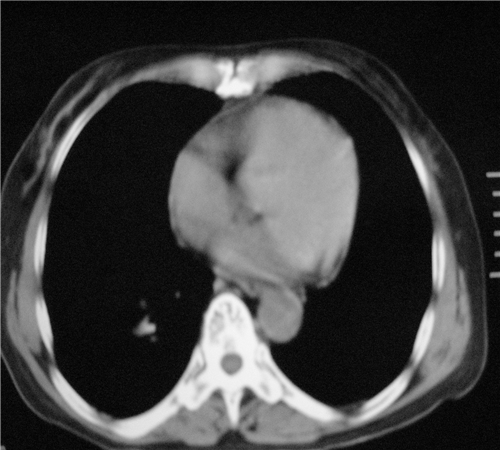

标题: CT26849:女67岁反复胸痛两天余,临床考虑夹层。 [打印本页]

标题: CT26849:女67岁反复胸痛两天余,临床考虑夹层。

右肺感染,未见夹层。

升主动脉增宽是怎么回事啊!食管有事吗?老师

既然考虑夹层,建议强化!另:右下肺感染!

1)右肺感染性病变。2)建议行ct增强扫描或mri检查排除主动脉夹层。

双下肺感染,右侧显著。有无夹层,增强扫描后再诊断。

1. 感染性病变,2.未见夹层,3.食道未见异常。

平扫未见确切夹层征,建议必要时增强扫描或mri检查。